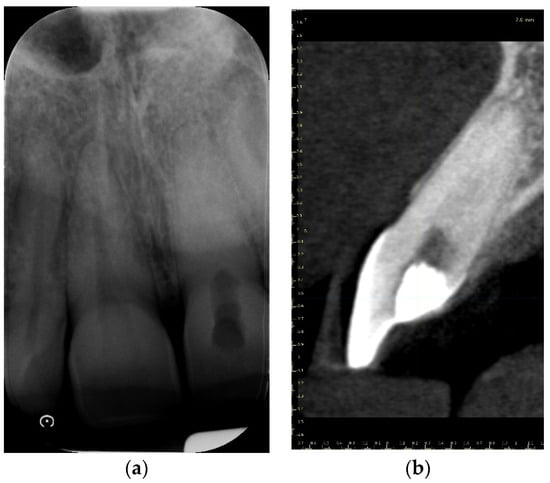

A 39-year-old male patient was referred to an endodontic specialist for the treatment of a maxillary left central incisor (tooth 21) before prosthetic treatment. Endodontic treatment had been initiated by the referring dentist, but as it was impossible for the clinicians to localize the root canal under the optical microscope, the treatment could not be completed, and the patient was referred to a specialist. The patient’s medical history revealed the absence of any systemic disorders or allergies. The dental history revealed trauma to the maxillary anterior region in childhood and subsequent gradual discolouration of the maxillary left central incisor. The patient presented with no complaints. Clinically, there were no pain or sensitivity to percussion or palpation. Tooth mobility was not increased. The tooth was restored by the referring dentist with a temporary restoration (composite resin) and showed no response to the pulp sensibility test (cold test). The radiograph and CBCT images showed that the endodontic treatment was initiated with wide access in the coronal part and confirmed root canal obliteration (Figure 16). After discussing the high probability of perforation and further tooth substance loss, an endodontic guide was designed.

Figure 16. The failed wide access in the coronal part and root canal obliteration on (a) X-ray and (b) CBCT images.